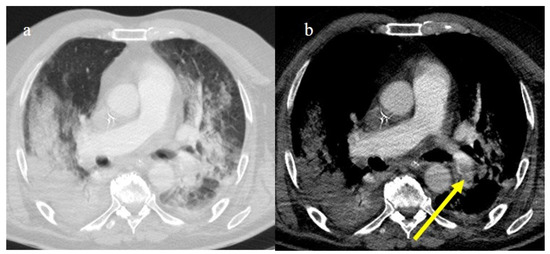

3.3.1. Acute Respiratory Distress Syndrome

3.3.2. Pneumomediastinum and Pneumothorax

3.3.4. Pulmonary Thromboembolism